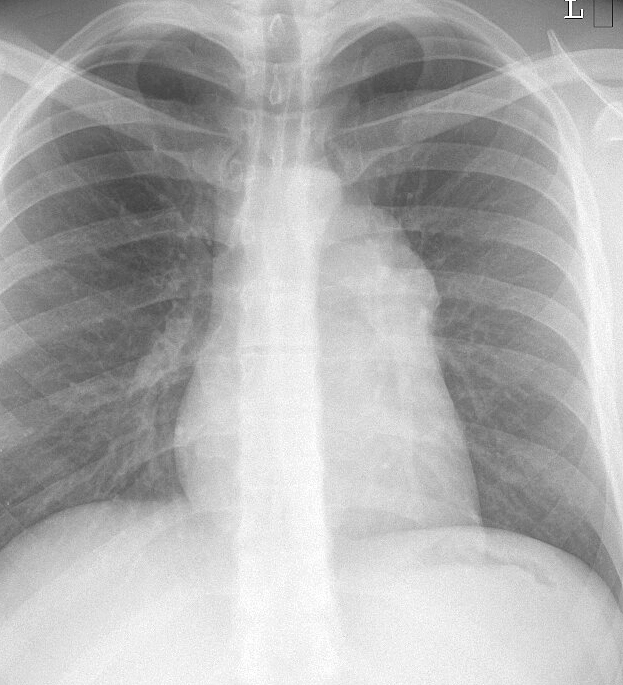

Thymoma